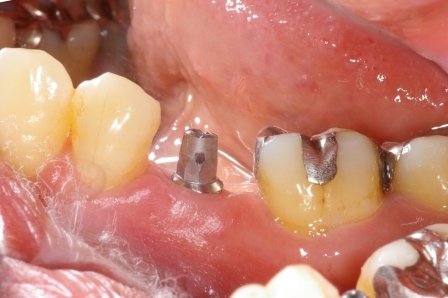

インプラント(人工の歯根)を入れた症例です。

歯の根っこにひびが入り、抜歯となった左下にインプラント(人工の歯根)を使って歯を入れました

前後の歯を削らずにすみます